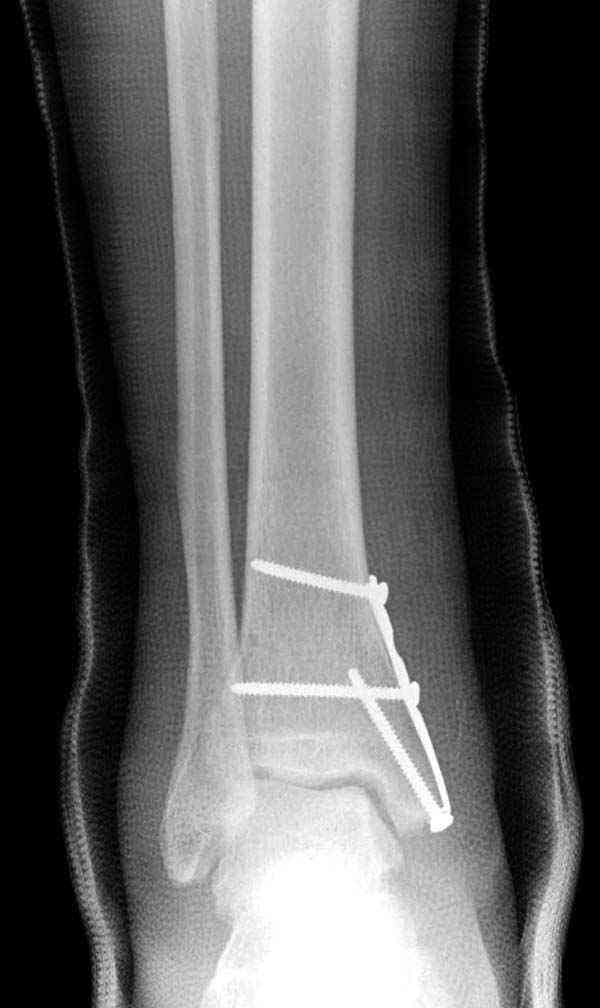

Случай прошлого года:пациентка-молодая ,крупная женщина ,30лет.Травма в начале апреля 2009г-пронационный перелом лодыжек с подвывихом стопы.Ко мне обратилась через 35 дней,прооперирована 22.05.2009г.Внутренняя лодыжка фиксирована по Веберу,наружная реконструктивной пластиной с наложением болта-стяжки.Иммобилизация "сапожок" в течении месяца,затем пригипсовано "стремя".Гипс снят 10.07.2009г

Достаточно быстрое восстановление функции.В октябре 2009г-почувствовала боль,в области рубца над гайкой открылся свищ.На Р-граммах-консолидация переломов и смещение гайки по стяжке.10.11.2009г-конструкции удалены,санация,заживление ран.В настоящее время пациентку ничего не беспокоит.На операции-раскручивание гайки-болталась на конце стяжки.Вопросы:какой механизм раскручивания и что я неправильно сделал?Свои версии:1)в области синдесмоза успела образоваться рубцовая ткань,которая при движении в суставе"пружинила",поскольку голеностопный сустав является спиральным, то и биомеханика подобна кривошипному механизму.2)Реконструктивная пластина не "реконструировалась" по форме лодыжки.Наложил,как есть.То есть подпружинивала сама пластина.Ну,это мои догадки.Что нужно,чтобы избегать впредь таких,пусть и не "страшных"осложнений:Рассверливать через лодыжку область синдесмоза?Ставить шайбу-гровер?Тщательно моделировать пластину?Прилагаю сравнительные снимки-сразу после операции и перед удалением конструкции.

Визуально никаких вопросов по репозиции не было.Да и на основании чего сомнения,что наружная лодыжка не полностью репонирована или прорезалась проволка ???Я не вижу...Снимок после репозиции справа.